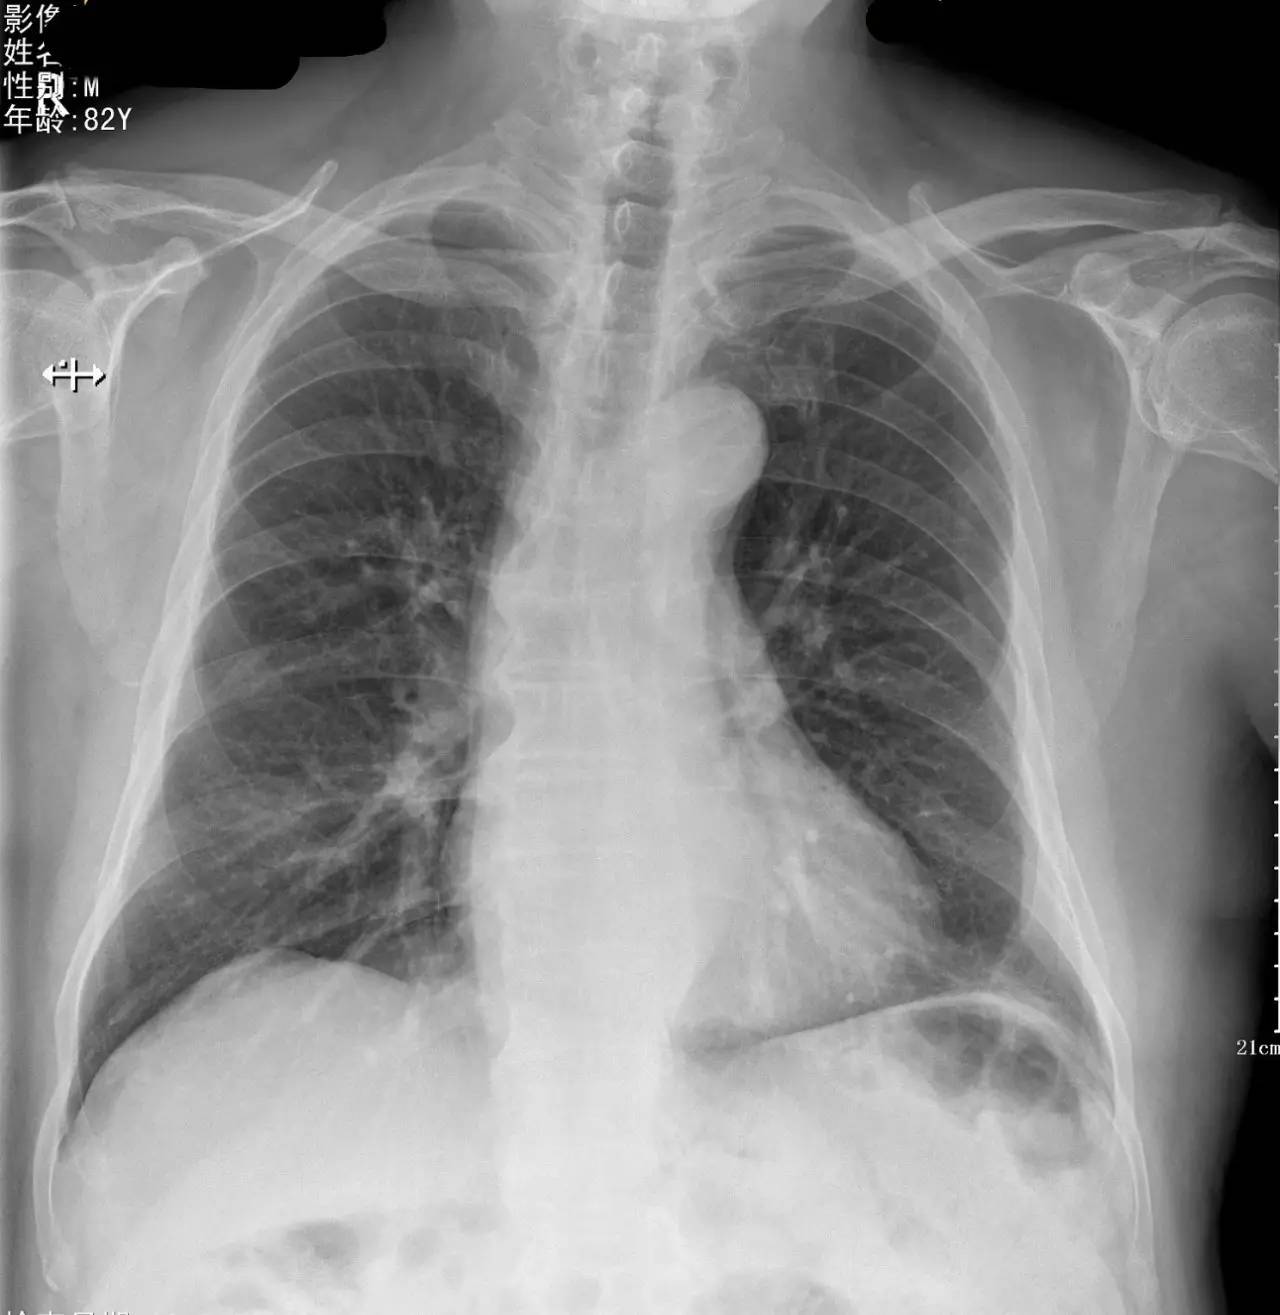

>>>>病例1:男 82岁 体检,患者自述无任何不适。

左下肺最有可能的诊断是?

A.包裹性积液

B.胸膜增厚

C.胸腔积液

D.心包脂肪垫